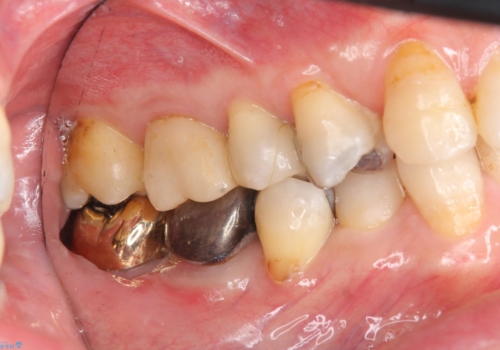

下の奥歯の虫歯 歯周外科手術を含めた治療

- 右下奥の銀歯の下が虫歯になっていました。

歯ぐきの下までしっかり修復するために、歯周外科手術を含めた治療を行いました。